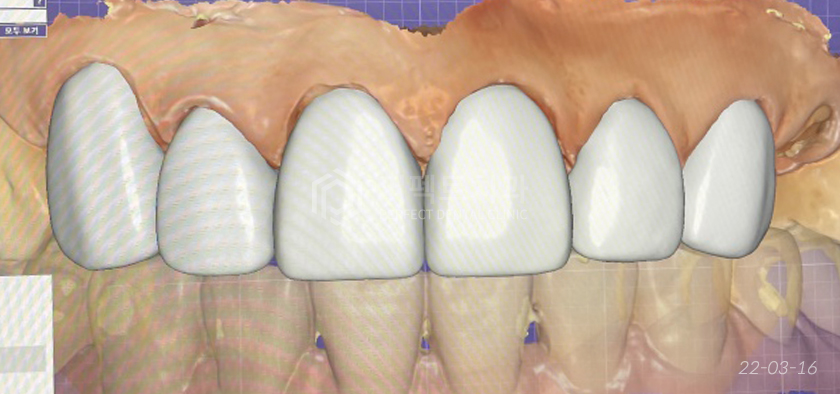

검사 후 상담을 해본 결과, 환자분께서는 재보철을 하면서 잇몸 경계부위를 더 깨끗하게 개선하고 싶다고 하셨습니다.

또 치아의 색은 기존보다는 더 밝은 색상을 선택하셨고 치아 형태는 환자분에게 디자인 과정을 보여드리며 결정되었습니다.